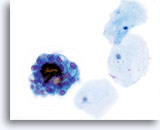

Abnorme Endometriumzellen (NOS)

(51-jährige Patientin, letzte Periode unbekannt) Es ist ein lockerer, dreidimensionaler Verband aus Drüsenzellen zu sehen, mit vergrößerten, runden bis ovalen Kernen, glatten Kernmembranen und aufgehelltem Chromatin.

60x

Biopsie – Benignes proliferierendes Endometrium

Abnorme Endometriumzellen (NOS)

(51-jährige Patientin, letzte Periode unbekannt) Es ist ein lockerer, dreidimensionaler Verband aus Drüsenzellen zu sehen, mit vergrößerten, runden bis ovalen Kernen, glatten Kernmembranen und aufgehelltem Chromatin.

60x

Biopsie – Benignes proliferierendes Endometrium